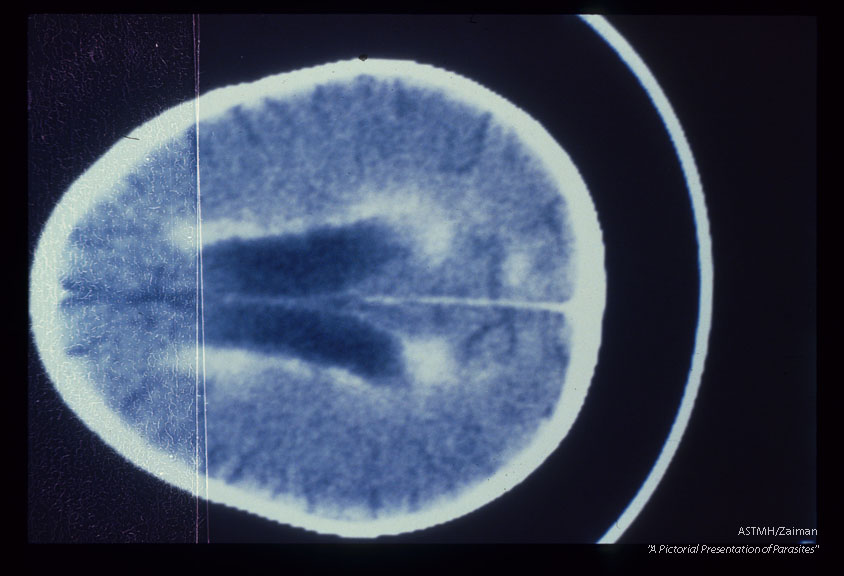

Samecase. Contrast enhanced CT brain scans show ventricular dilatation, periventricular enhance­ment and enlargement of cortical sulci.

Description: Samecase. Contrast enhanced CT brain scans show ventricular dilatation, periventricular enhance­ment and enlargement of cortical sulci.